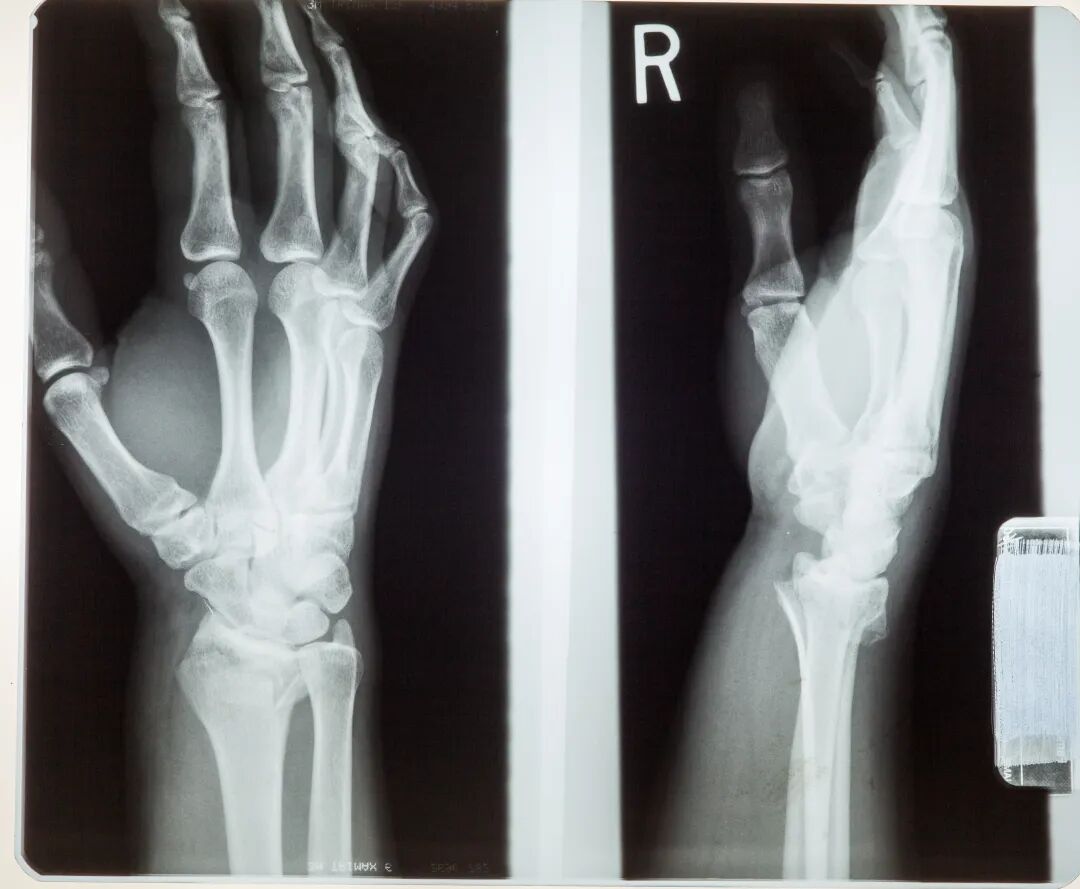

骨质疏松症是一种以骨量低下、骨微结构损坏,导致骨脆性增加、易发生骨折为特征的全身性骨病。它被称为“静悄悄的流行病”,因为骨骼在不知不觉中变得脆弱,往往在第一次骨折后才被发现。

一、骨质疏松的危害远不止“腰酸背痛”  许多人认为骨质疏松是小事,只是年纪大了的普通现象。事实上,它带来的最大危害是骨折,即“脆性骨折”。一个轻微的碰撞、跌倒,甚至打个喷嚏、弯腰捡东西,都可能导致骨折。最常见的部位是:  · 髋部骨折:被称为“人生最后一次骨折”,致残率和死亡率高,严重威胁老年人生命健康。 · 脊柱骨折:导致身高变矮、驼背,并引起慢性顽固性背痛。 · 腕部骨折:常见于摔倒时用手撑地。